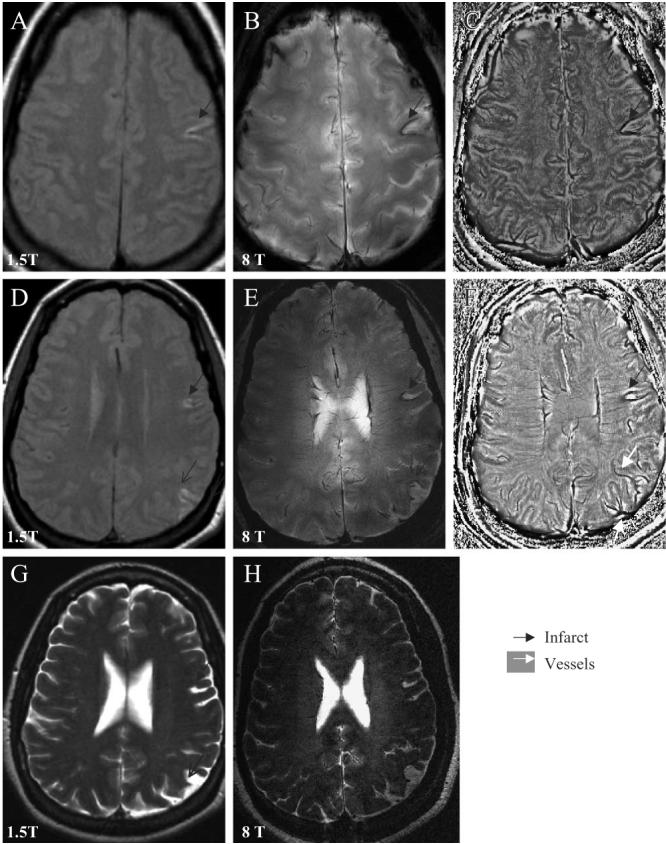

Fig. 1.

Axial slices through the cortex show the left temporal infarct (black arrow) with iron deposits surrounding the infarct site, the old parietal infarct (black thin arrow) on the 1.5-T T1-weighted FSE images (A, D), 8-T GE magnitude images (B, E) and the corresponding phase images (C, F). Asymmetry of the vascular supply in the infarcted and noninfarcted hemispheres, and venous drainage to the left parietal infarction are better seen on the 8-T GE phase images (C, F). The 1.5-T T2-weighted FSE image (G) and 8-T RARE image (H) reveal of the left frontal, temporal (black arrow) and parietal infarcts (black thin arrow). The 8-T GE: BW=50 kHz, FOV=20×20 cm2, slice thickness=5.0 mm, TR=528.3 ms, TE=7.0 ms, matrix 512×340, flip angle=20°. The 8-T RARE: BW=69.4 kHz, FOV=20×20 cm2, slice thickness=2 mm, TR=3000 ms, TE=2 ms, matrix 512×512, flip angle=68°. The 1.5-T T1-weighted FSE: slice thickness 5 mm, TR=500 ms, TE=14 ms, FOV=22×22 cm2, matrix=256×192, number of slices=16; 1.5-T T2-weighted FSE: slice thickness=5 mm, TR=7000 ms, TE=105 ms, FOV=22×6 cm2, matrix=128×128, number of slices=16.

4.1. The 1.5- and 8-T MRI of stroke

Fig. 1 shows 8- and 1.5-T MR images that were acquired from a 40-year-old woman 1 year after the acute ischemic stroke that presented as expressive aphasia, right-sided numbness that resolved with a minor deficit (Table 1, case 1). The cortical left temporal infarct and old left parietal and left frontal infarcts were seen on the axial slices through the cortex on the 1.5-T T1-weighted FSE (A, D) and T2-weighted FSE (G) images, as well as on the 8-T GE (B, E) and 8 T RARE (H) images. The 8-T GE magnitude images (B, E) were processed using the phase enhancement method [14] to create the phase images (C, F). The left temporal infarct had a typical V shape on both 1.5- and 8-T images. Both magnitude and phase GE images at 8 T showed hemosiderin deposits surrounding the infarction. Medullary veins had normal, signal-void pattern, perpendicular to the ventricles. Phase images (C, F) showed that vascular patterns in the infarcted hemisphere were more prominent compared to the noninfarcted hemisphere and displayed venous drainage to the left parietal infarction. Delineation between the gray and white matter and vascular patterns were enhanced on the 8-T phase images compared to magnitude images. High-resolution axial 8-T GE magnitude images (Fig. 2) display the details of the left temporal and parietal infarcts described in Fig. 1. The infarction is surrounded by a low-signal intensity area, suggestive of intraparenchymal iron deposits (A–D). Normal-appearing medullary veins were seen as linear signal voids perpendicular to the ventricle (C). Small vessels crossing or adjacent to the infarctions (C, D) appeared prominent compared to vasculature in the noninfarcted hemisphere, which may be suggestive of blood flow alteration or a higher deoxyhemoglobin content (D–F).

Fig. 2.

High-resolution axial 8-T GE slices display details, consolidation and venous drainage of the left temporal (A–D) and parietal infarctions (E, F), shown in Fig. 1. Infarctions with high-signal intensity are surrounded by a low-signal intensity area, suggestive of iron deposits extending into the white matter. Normal-appearing medullary veins and cortical penetrating veins are seen as signal voids (white arrow). Details of vascular patterns in the left parietal infarction are seen on slices E and F. The 8-T GE: BW=69.4 kHz, FOV=20×20 cm2, slice thickness=2.3 mm, TR=602.7 ms, TE=10.0 ms, matrix=1024×1024, number of slices=18.